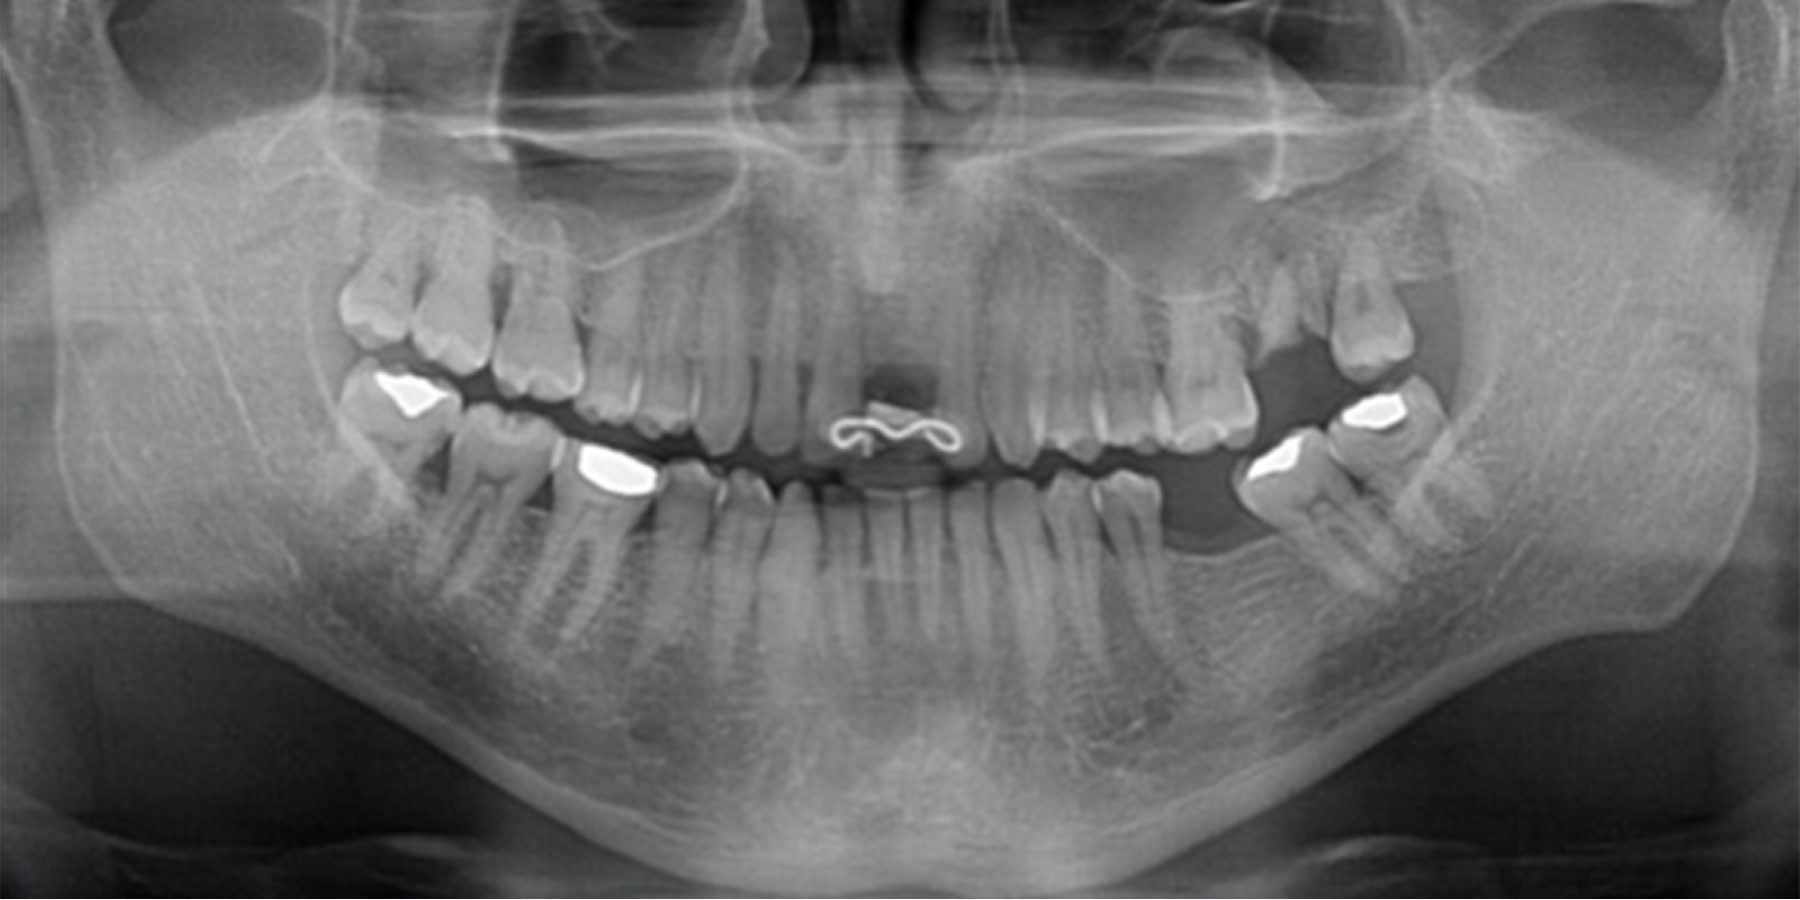

The orthopantomography analysis confirmed the absence of teeth 21 and 36 as well as the presence of root fragments of molar 27 and a defective restoration in 38 (Figure 3). The study models analysis, mounted in a semi-adjustable articulator, revealed a discrepancy between centric relation and maximum intercuspation records (Figure 4A-B).

Figure 3